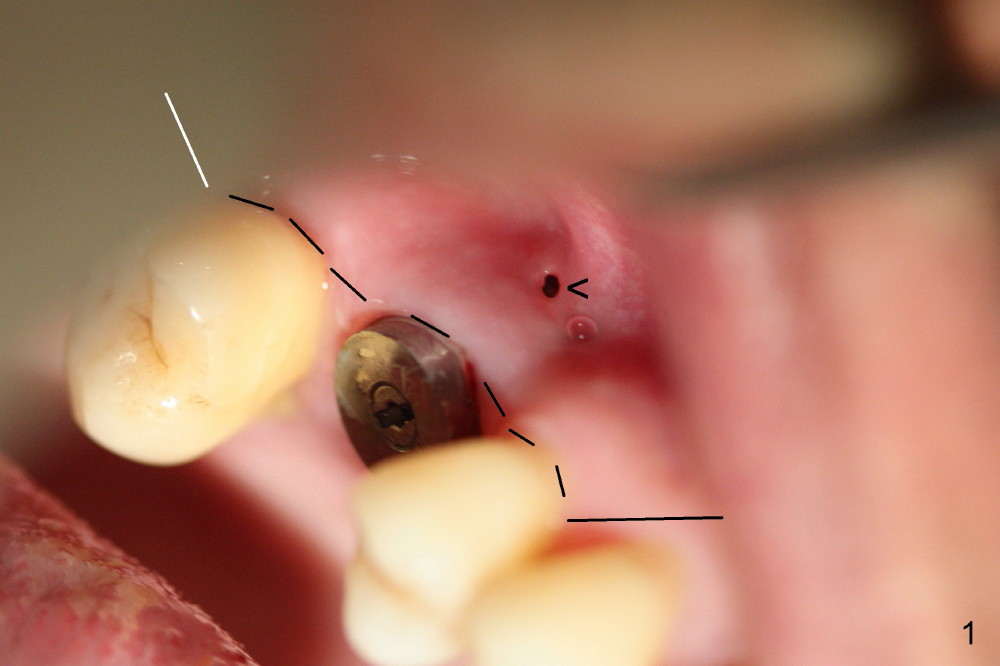

The surgery is finished as planned. Fig.2,3 (intraop photos) show thread exposure. The fistula is closed with perio glue. The defect appears to be a preexisting condition. Bone graft may be not enough or get infected. Or the implant is oversized, or placed too buccally (because of palatal defect).